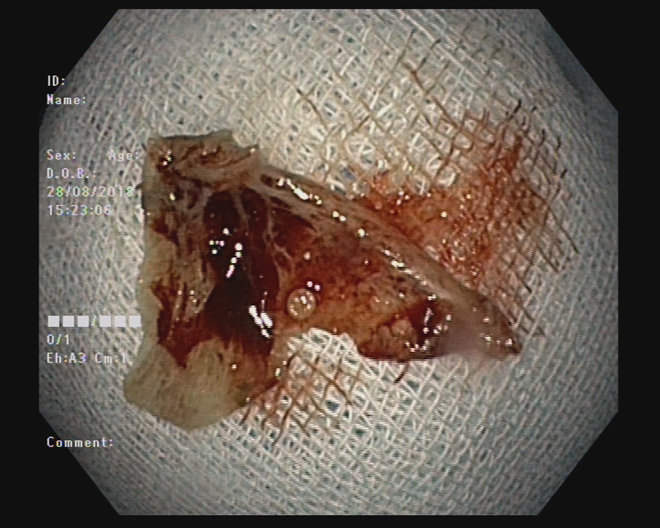

Mảnh xương cá đã được gắp ra ngoài qua nội soi.

Mảnh xương cá khi còn mắc kẹt tại miệng thực quản